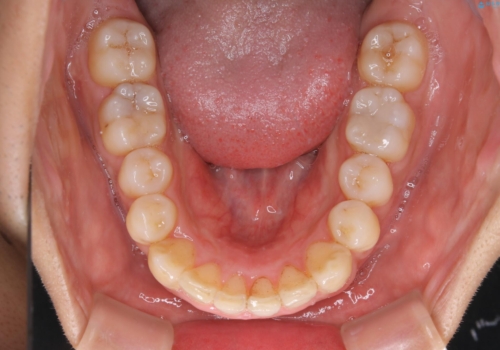

一見、表面はそこまで汚れが付着していないようにみえますが、裏面を見てみると、着色や歯石が多く付着していました。個人差はありますが、3カ月に1回の来院でもここまで汚れが付着する為、メンテナンスやクリーニングは、3ヶ月に1回をおすすめします。